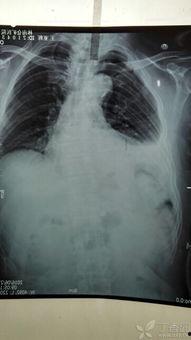

肋骨骨折,听起来是不是很严重?其实,它并不像你想的那么可怕。肋骨骨折是指肋骨因外力作用而发生的断裂,常见于胸部受到撞击或挤压的情况下。据统计,每年全球约有数百万人遭受肋骨骨折的困扰。